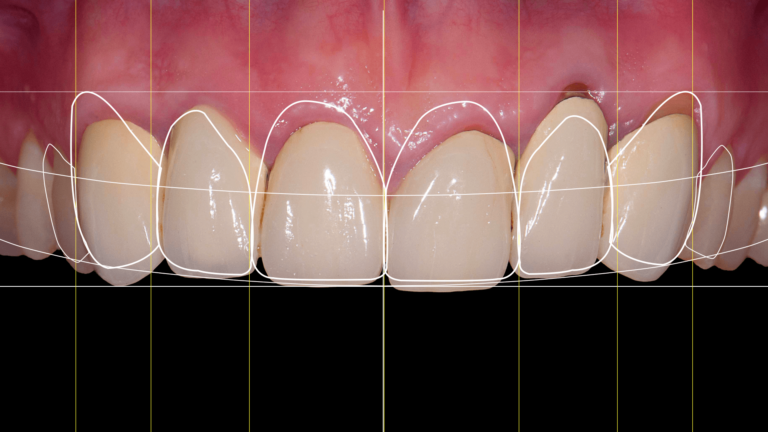

Czym jest elektrokoagulacja? Elektrokoagulacja to zabieg polegający na kontrolowanym wykorzystaniu prądu elektrycznego w celu zamknięcia naczyń krwionośnych oraz usunięcia zmienionych tkanek. W stomatologii metoda ta znajduje zastosowanie przede wszystkim w chirurgii i periodontologii. Stomatolog w nowoczesnej klinika stomatologiczna Kraków wykorzystuje…